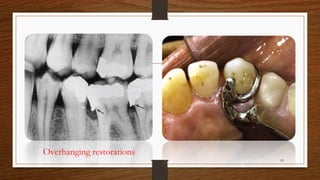

Overhanging restorations

• Rapidly progressive lesions occur most frequently in interproximal areas' and

are usually associated with areas of greater plaque accumulation and

inaccessibility to plaque control measures (e.g., furcation areas, overhanging

margins, sites of malposed teeth, or areas of food impaction).